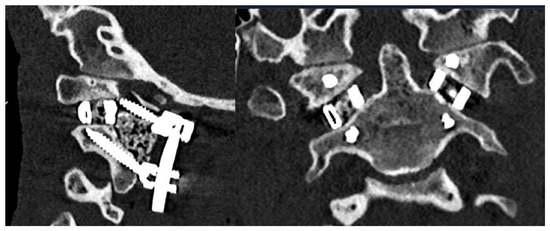

3.1. Preoperative Planning and 3DPI Design

3.2. Surgical Approach